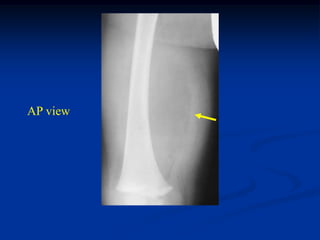

Case #1189 2 yearmale with intramuscular lipoma posterior thigh